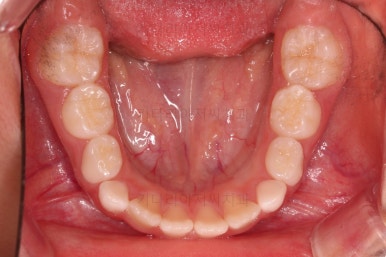

4. 마무리

부산어린이교정 키다리아저씨치과에서 앵글씨 3급 부정교합 및 반대교합이 잘 개선되었습니다.

심지어는 치열을 정교하게 맞추는 기능이 있는 장치는 아니지만, 자연스럽게 맹출 경로를 잡아줌으로써 앞니 치열도 매우 고른 양상이 되었습니다.

전후 비교해 보겠습니다.

웃을 때 드러나는 치열도 좋아졌네요.

향후에는 호흡기 및 혀 위치로 인해 재발이 되지 않는지를 중점적으로 체크해 나가게 됩니다.